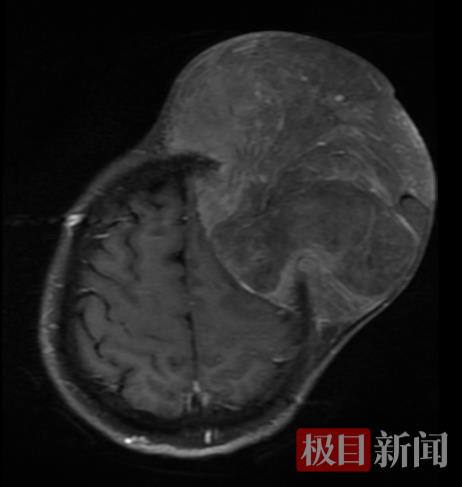

将李女士收治入院后,陈治标主任团队为她完善了相关检查。影像检查结果令人十分担忧:肿瘤组织不仅巨大,且已侵蚀颅骨。陈治标主任表示,无痛肿块突然加速生长,伴随头痛、肌力下降等神经系统症状,以及影像显示“啃噬样”骨破坏等,都是相当反常的信号。如果放任不管,肿瘤细胞可能会经血液或淋巴进行全身转移,或者肿瘤压迫脑功能区导致永久性瘫痪、失语等功能障碍;如果肿瘤进一步增大,压迫脑组织导致头痛进一步加剧,会使得颅内压增高形成脑疝,将会直接危及生命。

术前

术后